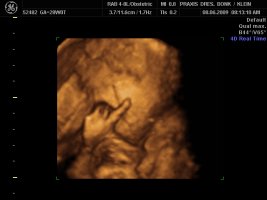

Und dann haben wir endlich unser Video gemacht, Zeit hatten wir ja nun genug und das ist voll süß geworden, sie war wohl auch wie Mama müde, denn sie hatte öfter mal gegähnt und mit den Augen geblinzelt :love1 ...kann es kaum noch erwarten die Kleine in die Arme zu nehmen :applaus

Und wir haben endlich ein Beweisfoto bekommen, dass es ein Mädchen ist...

Hier ein paar Bilder von Montag, neben dem Video haben wir auch sehr viele Bilder mitbekommen.... :love1

Anhänge

• Bild 1.jpg

Bild 1.jpg

72,4 KB · Aufrufe: 72

• Bild2.jpg

Bild2.jpg

75,1 KB · Aufrufe: 72

• Bild3.jpg

Bild3.jpg

61,5 KB · Aufrufe: 72

@Imke ui was für schöne Bilder, will auch! *jammer*